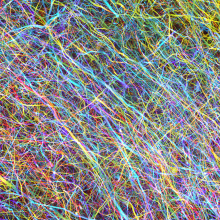

To understand how the brain works, scientists need to map how nerve cells (neurons) are wired to form circuitries in both healthy and disease states. Traditionally this was accomplished by serial cutting of brain tissue into thin slices and tracing the cut nerve fibres over many sections. However, this approach is difficult and labour-intensive as the neuronal circuitries span across great distances in three dimensions (3D) and are tightly entangled microscopically. To avoid the sectioning of tissues, tissue clearing techniques – methods that turn opaque tissue transparent – have been developed, enabling high-resolution and deep imaging of neuronal circuitries. Although such techniques have been very effective on rodent brain tissue, only limited studies have found success with human brain tissue. The difficulties and challenges may be attributed to fundamental differences between the human and the mice brain.

To overcome these barriers, the team developed a new tissue clearing solution, OPTIClear. OPTIClear selectively adjusts the optical properties of tissue without damaging or changing their structural components. Combined with fluorescent staining and other tissue processing methods, the team created a simple yet versatile tool for the study of microscopic structures in the human brain. Nerve cells, glial cells, and blood vessels were visualized in exquisite detail, with their 3D relationship determined. For example, the team performed 3D morphological analysis on human brainstem dopaminergic neurons in the millimetre scale, and imaged more than 3,000 large neurons in the human basal forebrain in merely five days, which normally is extremely laborious and takes at least three weeks. These neurons have been implicated in neurological and psychiatric diseases such as dementia and depression; the promising results suggest that this novel method is applicable to future research on these conditions. More remarkably, OPTIClear can also be applied in both archived (>30 years) and clinical specimens.